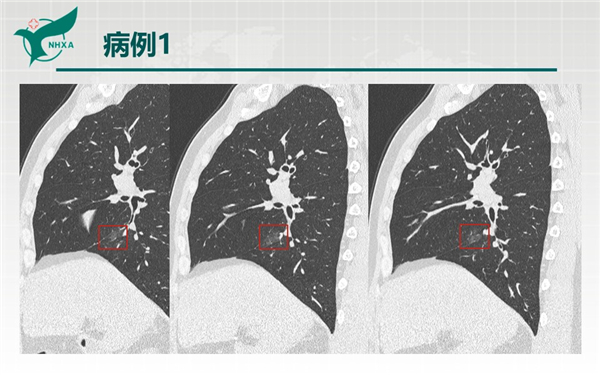

【病例分享】新型冠狀病毒肺炎3例(西安市第九醫(yī)院)

幻燈片10.jpg